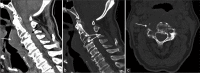

Figure 6:

Lateral projection of cervical spine radiograph. Lytic cervical spine lesion at C3 level with partial vertebral collapse (black arrow). It was associated with prevertebral soft-tissue swelling spanning from C2 to C4 levels (white arrow).

Figure 7:

(a) Plain CT cervical spine. Cervical spine tumor at C2–C3 levels. It was associated with prevertebral soft-tissue mass spanning across C2–C4 levels with intratumoral calcifications within (white arrow). There was epidural involvement at the anterior epidural space (black arrow). (b) Plain CT cervical spine. Bone destruction at C2 and C3 vertebrae. (c) Plain CT cervical spine. Involvement of the right C3 neuroforamen.

Figure 8:

Contrast CT cervical spine. Encasement of the right vertebral artery which remained opacified (black arrow).